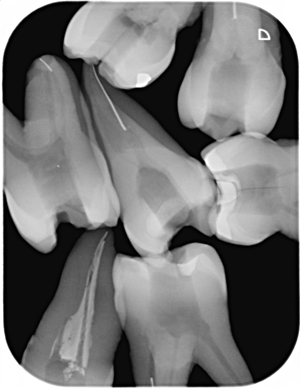

幸い開業医には抜いた歯がありますから、これでも練習できます。下の画像は根管内でファイルを故意に破折させて除去の練習に使ったときのレントゲンです。

こんなふうに撮影できたら、CTがなくても根管に関しては大丈夫なんですけどね。上の写真は上顎小臼歯ですが、複雑な根管形態です。アップです。

破折ファイル除去のトレーニングを受ける前はチャレンジでしたが、今は根管から飛び出してくるファイルのイメージが湧いてきます。